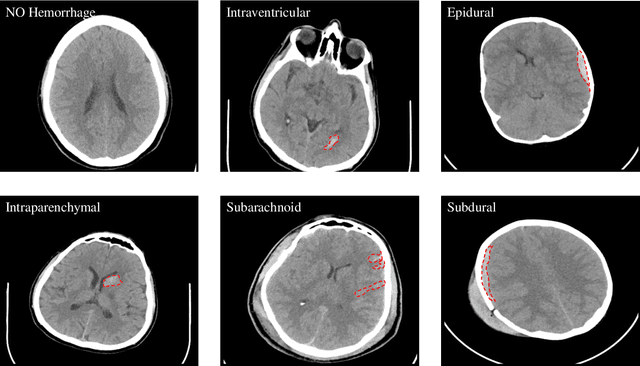

Abstract:Traumatic brain injuries could cause intracranial hemorrhage (ICH). ICH could lead to disability or death if it is not accurately diagnosed and treated in a time-sensitive procedure. The current clinical protocol to diagnose ICH is examining Computerized Tomography (CT) scans by radiologists to detect ICH and localize its regions. However, this process relies heavily on the availability of an experienced radiologist. In this paper, we designed a study protocol to collect a dataset of 82 CT scans of subjects with traumatic brain injury. Later, the ICH regions were manually delineated in each slice by a consensus decision of two radiologists. Recently, fully convolutional networks (FCN) have shown to be successful in medical image segmentation. We developed a deep FCN, called U-Net, to segment the ICH regions from the CT scans in a fully automated manner. The method achieved a Dice coefficient of 0.31 for the ICH segmentation based on 5-fold cross-validation. The dataset is publicly available online at PhysioNet repository for future analysis and comparison.